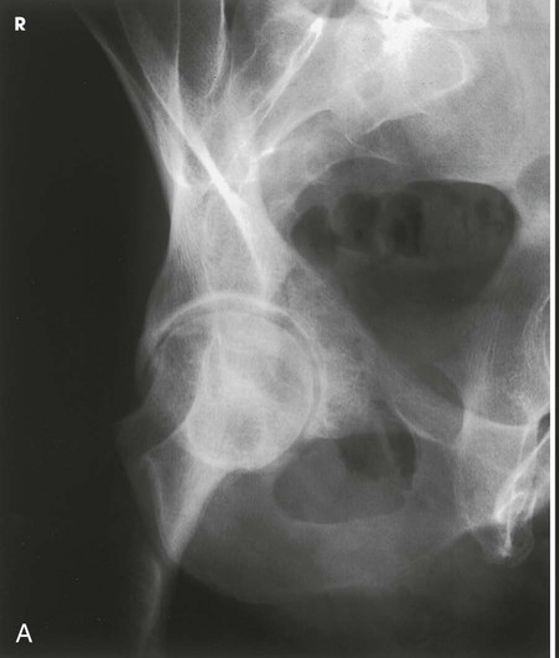

AP Oblique Projection; Acetabulum; Judet Method; RPO and LPO Positions (CR & SS)

Internal oblique - Perpendicular to the IR and entering 2 inches (5 cm) inferior to the ASIS of the affected side

The internal oblique position is used for a patient with a suspected fracture of the iliopubic column (anterior) and the posterior rim of the acetabulum

The resulting image shows the acetabular rim

(Note: Both images are performed to demonstrate the entire acetabulum as well as the iliopubic and ilioischial columns of the affected side)

POSITIONING: AP Oblique Projection; Acetabulum; Judet Method; RPO and LPO Positions (Internal Oblique for Right Hip)

AP Oblique Projection; Acetabulum; Judet Method; RPO and LPO Positions (Eval Criteria)

• Evidence of proper collimation

• Acetabulum centered to the IR

• The iliopubic column and the posterior rim of the affected acetabulum on the internal oblique

• The ilioischial column and the anterior rim of the acetabulum on the external oblique

• Soft tissue and bony trabecular detail

AP Oblique Projection; Acetabulum; Judet Method; RPO and LPO Positions (Internal)